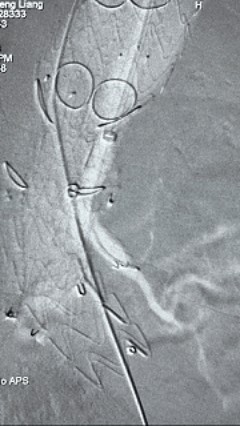

4. 经长鞘导入导管后,超选入腹腔干动脉,送入先健覆膜支架10*80mm一枚,近端重叠内分支,远端重叠腹腔干动脉,并予以10mm球囊后扩,手推造影显影良好。

3.gif

5. 撤出腹腔干导丝导管,经左肱动脉长鞘继续抓捕预置导丝将长鞘超选至另一侧内分支,后超选进肠系膜上动脉,沿导丝送入先健覆膜支架10*100mm一枚,近端重叠内分支,远端重叠于肠系膜上动脉,并予以10mm球囊后扩,手推造影显影良好。

8.gif

6. 解除束径,打开近端后释放,经肱动脉长鞘超选支架外分支,并进一步超选右侧肾动脉,交换加硬导丝,送入覆膜支架6*50mm和7*60mm各一枚,并予以球囊后扩张,手推造影显影良好。

11.gif    12.gif